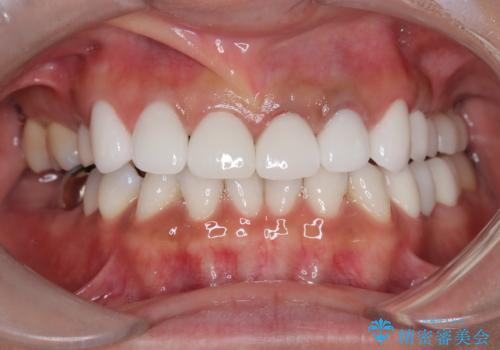

【オールセラミッククラウン】前歯を白くきれいにしたい。

- 前歯の変色を主訴に来院されました。

歯茎のラインも整っていなかったため、手術を行いきれいな被せ物をいれることができました。

歯茎のラインを整える手術を行ったあとは、しばらく待ってから被せ物の治療を行っていきます。